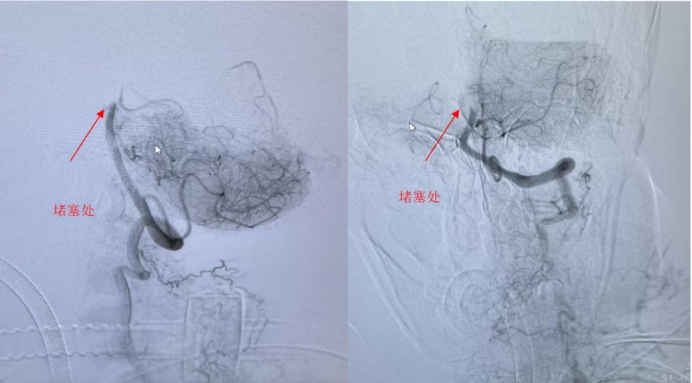

2026-03-22五院技术 | 90岁老人突发脑梗,黄金时间窗内"双管齐下"成功获救!

近日,广医五院卒中中心成功救治一名90岁高龄急性脑梗死患者。患者因基底动脉闭塞导致后循环梗死,病情凶险,随时危及生命。在神经内科、神经外科、急诊医学科、医学影像科团队协作下,患者接受…